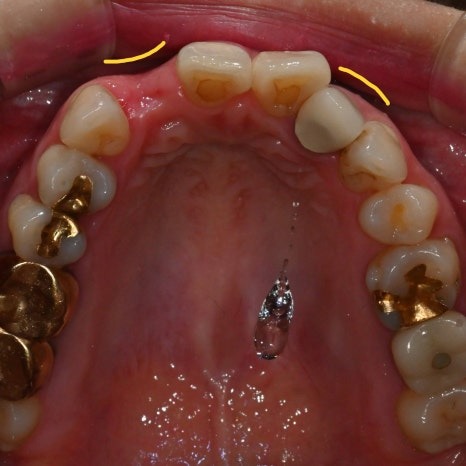

치아를 발치하고 나면

잇몸뼈가 빠른 속도로 위축되기 때문에

왼쪽 사진처럼 잇몸이

오목한 모양이 되어

심미적이지 못하게 될 뿐더러

음식물이 낄 수도 있습니다.

반대편 같은 위치아 앞니 잇몸처럼

볼록한 모양이 되어야

보기에도 좋기 때문에

임플란트 식립과 더불어

골이식도 동시에 진행하기로 합니다.